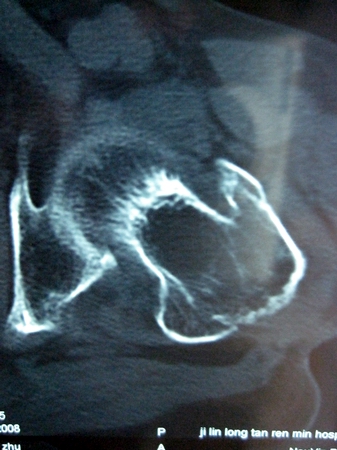

以下是引用lkc8963在2008-12-19 21:19:00的发言:[br]左?右?患侧大转子上移,股骨颈骨质浓杂,髋周见多发条片状骨化影,以小转子为著,多为陈旧性股骨颈骨折后改变并骨化性肌炎.请咨询既往史!